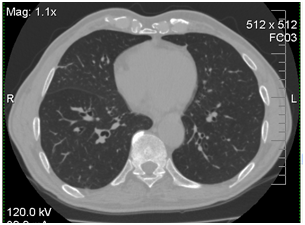

After 7days of voriconazole therapy the patient had a marked improvement in his general health condition (no fever or cough). After 3month of antifungal treatment by CT was noted complete resolution of the mycotic pneumonia (Figure 3).